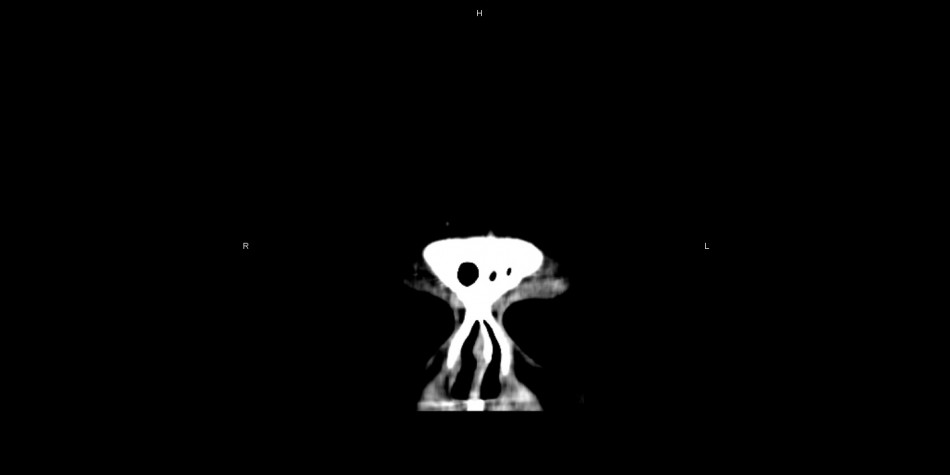

Card image cap